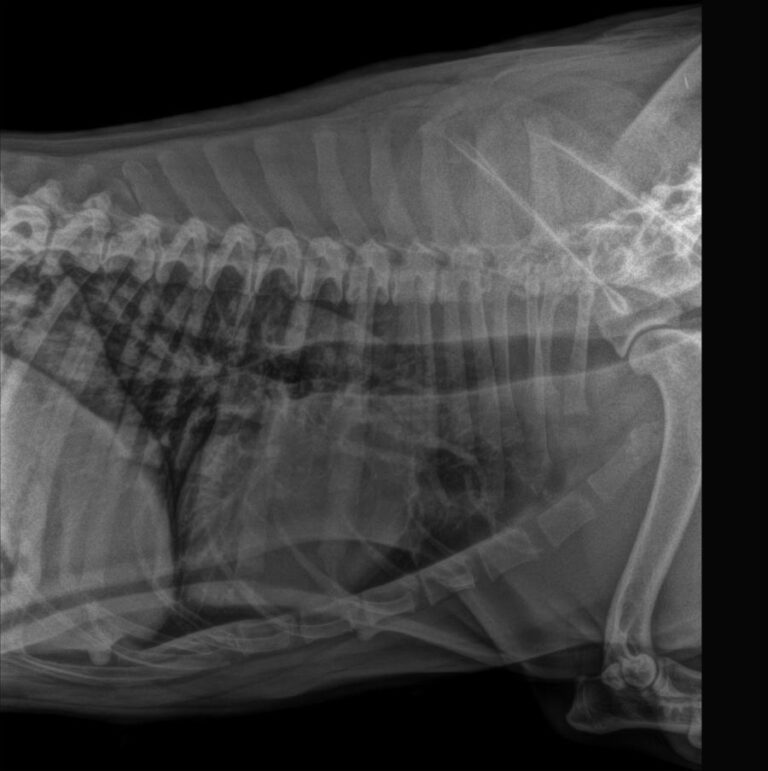

- Examen por imagen; ecografía de rutina y en caso de ser necesario, Rx, Tac o técnicas oftalmológicas.